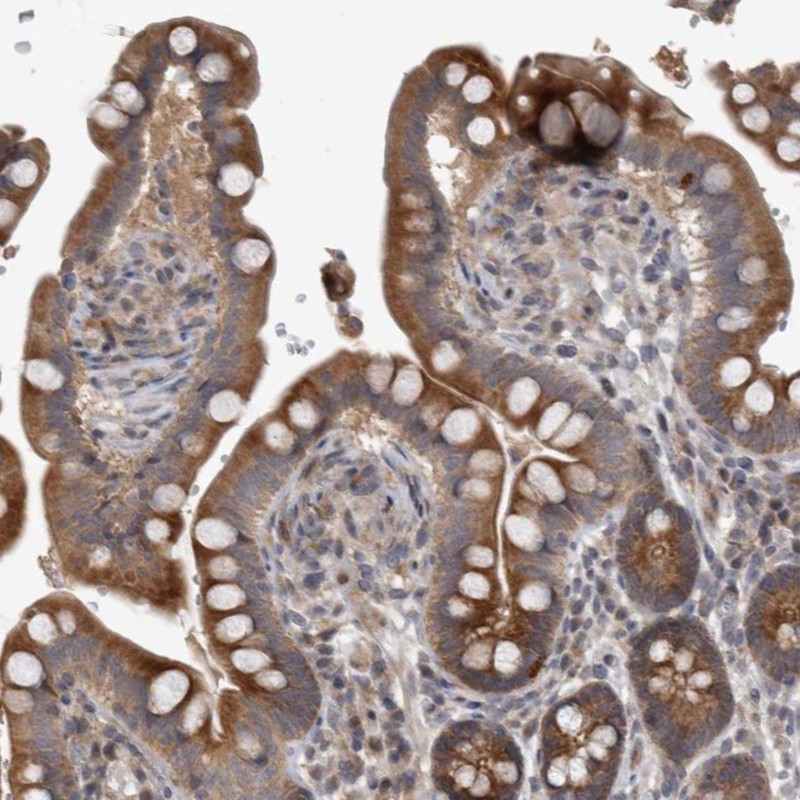

Immunohistochemical staining of human colon shows strong cytoplasmic positivity in glandular cells.